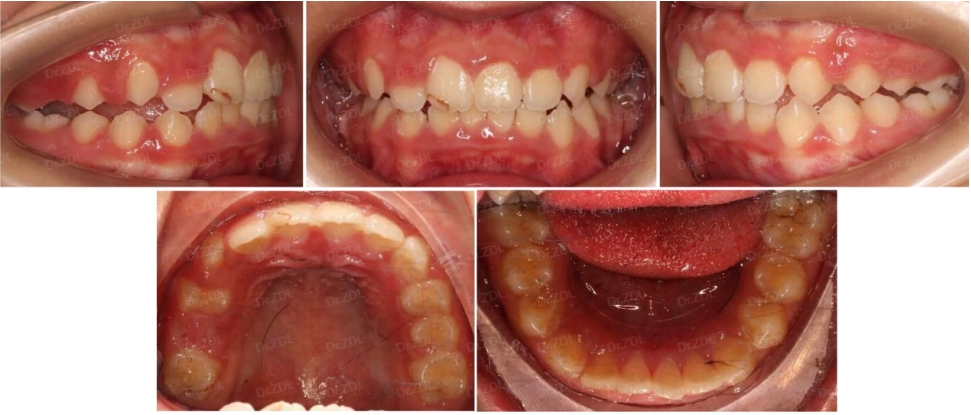

Grace硅胶牙套案例3:

这位小朋友,主诉牙凸、牙不齐、没下巴,临床检查看上前牙III度深覆合深覆盖,骨性II类倾向,上颌牙弓狭窄,鼻唇角偏大、颏唇沟比较深。

根据孩子牙齿情况,采用Grace轨道式硅胶矫治器,恢复上下颌正常牙弓宽度,匹配上下颌牙弓形态,引导上下恒牙正常萌出,引导下颌前伸,并日常辅助唇肌功能训练。

佩戴 Grace10 个月,上下颌牙齿排齐良好,咬合打开良好,深覆合深覆盖得到改善,侧貌形态良好。